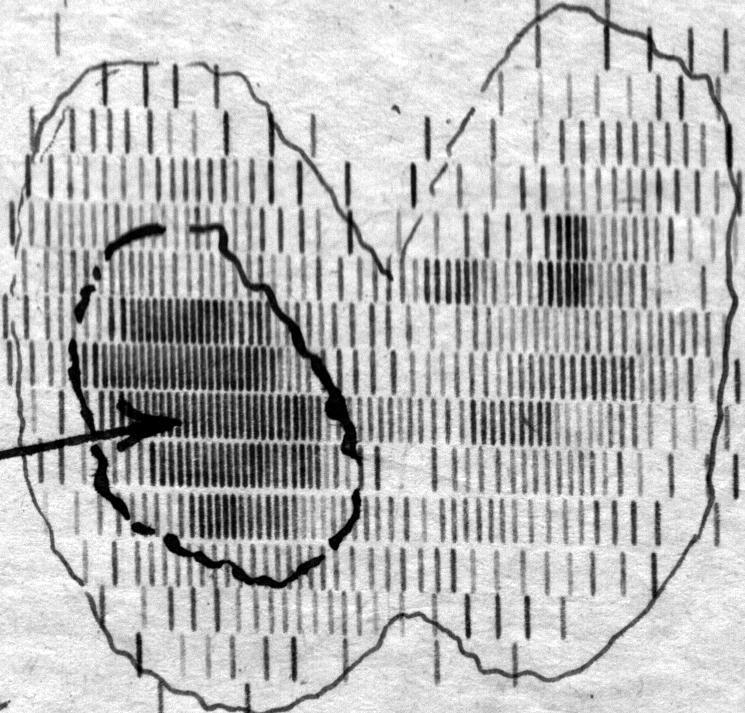

Радиоизотопная

сканограмма щитовидной железы